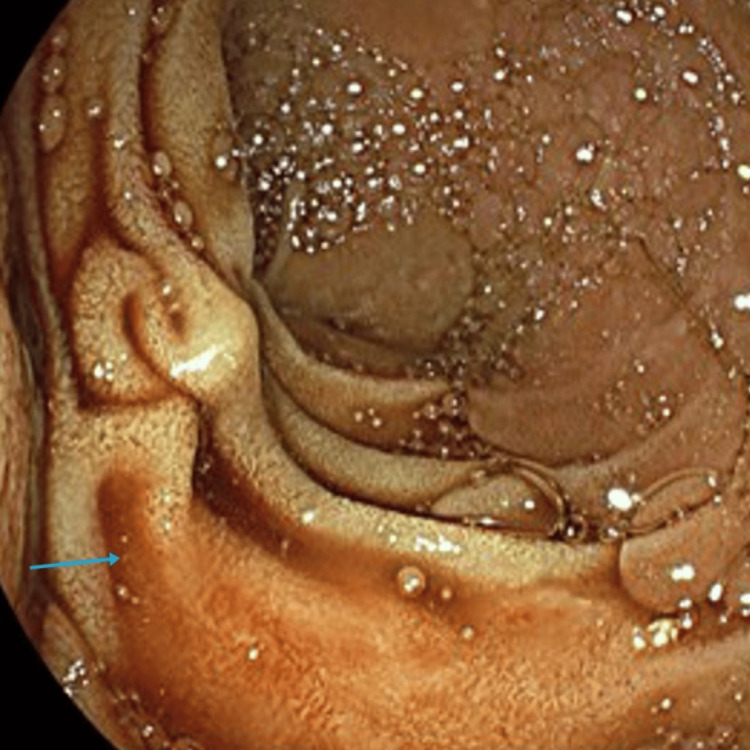

Since there were no stones found during ERCP and only clots were successfully evacuated with no concerns, an impression was made of stones that had spontaneously passed down the biliary tree. The initial blood culture grew Escherichia coli (E. coli), and in consultation with the microbiology team, the patient was prescribed intravenous meropenem and Tazocin based on sensitivities. Post-ERCP 15 hours later, she was reported by the nursing team to have per rectal bleeding with a drop in haemoglobin and persistently raised inflammatory marker, namely, C-reactive protein (CRP) of 25 milligrams per litre (mg/l) (reference range of 0-5 mg/l), and repeat blood culture grew vancomycin-resistant Enterococcus (VRE). In consultation with the microbiology team, her antibiotics were changed to linezolid and Tazocin. She had a repeat CT of the abdomen and pelvis that showed haemobilia (Figure 3).

The patient was transfused 2 units of red cell concentrate (RCCs), and an in-patient oesophagogastroduodenoscopy (OGD) was organised which showed blood in the duodenum that was successfully suctioned (Figure 4).